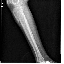

胫腓骨上段粉碎性骨折1(14.68MB)

胫腓骨上段粉碎性骨折2(10.09MB)

胫腓骨上段粉碎性骨折1

胫腓骨上段粉碎性骨折2